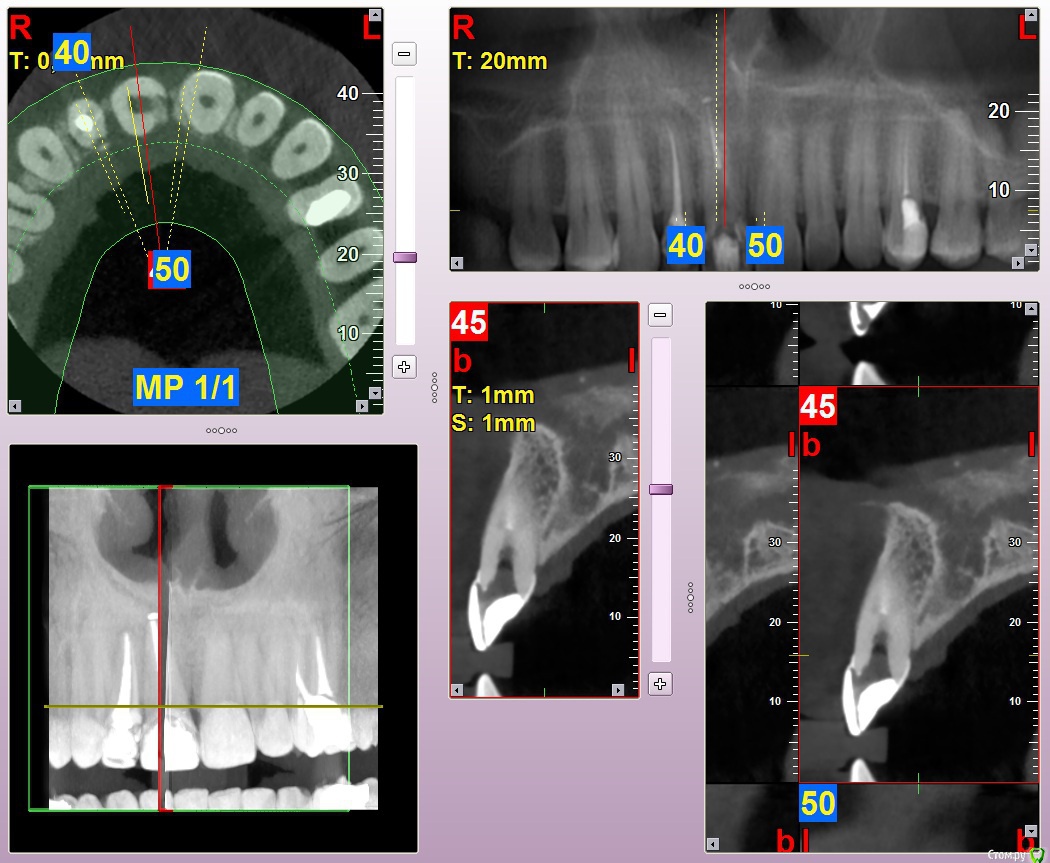

Kostoprav Опубликовано 8 июля, 2015 Автор Поделиться Опубликовано 8 июля, 2015 (изменено) продолжение истории) вот что было изначально а вот что получилось) временная реставрация она с ней до имплантации ходила, коронка на 12 тоже временная Изменено 8 июля, 2015 пользователем Kostoprav 3 Ссылка на комментарий

Kostoprav Опубликовано 8 июля, 2015 Автор Поделиться Опубликовано 8 июля, 2015 графт повторно после кюретажа засыпал) Ссылка на комментарий